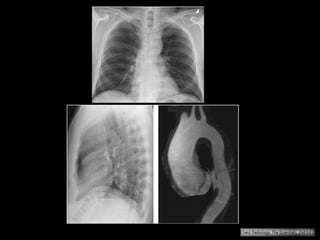

Trauma torácico: coice de um cavalo

História remota de acidente automotor